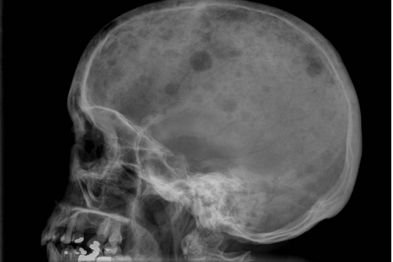

Learn more about the symptoms, causes, diagnosis, risk factors, and treatment of multiple myeloma. Background bone lesions are a key feature of multiple myeloma and for many years the conventional skeletal x‑ray survey following the paris. The hallmark biomarker in blood or urine is a monoclonal immunoglobulin, the monoclonal protein. Sometimes multiple myeloma is diagnosed when your doctor detects it accidentally during a blood test for some other condition. Multiple myeloma is a type of cancer of the blood that is formed in the bone marrow. Below the columns are the numbers of positive, negative and missing results of each imaging modality shown. Multiple myeloma is when plasma cells become cancerous and produce bone tumors called plasmacytomas. Symptoms and signs include anemia, skin lesions, weakness, and bone fractures. Multiple myeloma (kahler's disease) is a malignant plasma cell dyscrasia characterized by uncontrolled proliferation and the diffuse infiltration of monoclonal plasma cells in the bone marrow. Not all tests listed below will be used for every person. Multiple myeloma x ray skull. Multiple myeloma (mm), also known as plasma cell myeloma and simply myeloma, is a cancer of plasma cells, a type of white blood cell that normally produces antibodies. It sounds like a lot (and it is!) but none are that invasive or painful, with the exception of the bone marrow biopsy, but even that.

Multiple myeloma x ray skull. Bone marrow examination, including conventional cytogenetics and fluorescent in situ hybridization studies (fish). Multiple myeloma (kahler's disease) is a malignant plasma cell dyscrasia characterized by uncontrolled proliferation and the diffuse infiltration of monoclonal plasma cells in the bone marrow. The individual results of the different imaging methods performed at baseline for the 35 previously untreated multiple myeloma patients. Assigning a stage and a risk category.